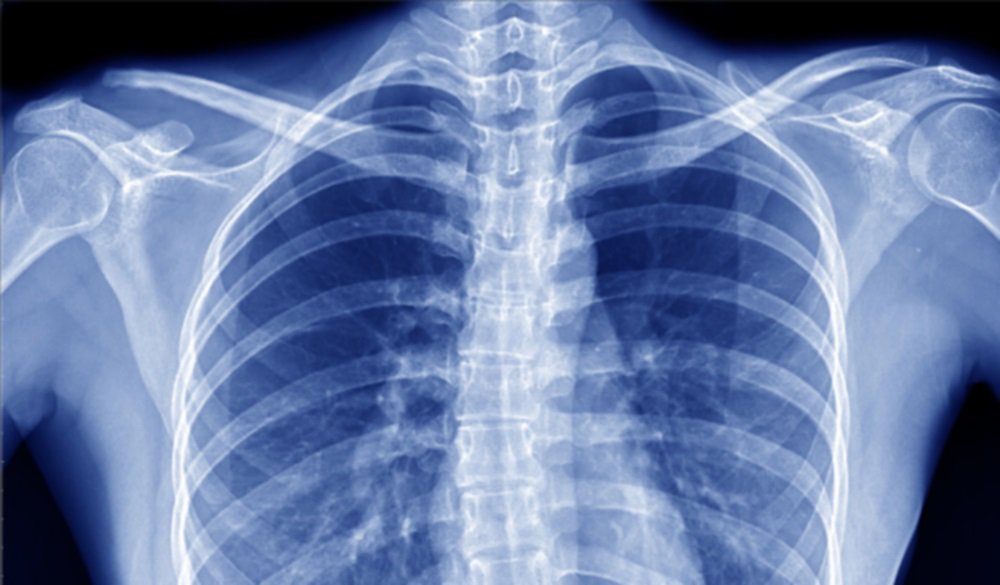

• عندما يتم تصوير الجسم من الداخل فإنه في تلك الحالة تزيل الأشعة السينية جمال المرء وحسنه.

• وذلك يعود إلى الدقة في تصوير شكل الجسم من الداخل حيث أنها تبرز شكل الهيكل العظمي بالكامل، وهذا يؤدي إلى إبراز شكل مغاير تمامًا لشكل الجسم من الخارج، وبالتالي تفقده جماله.

• تبرز صور الأشعة بيضاء اللون أما عن الأجزاء التي يتم فحصها فتكون سوداء اللون.